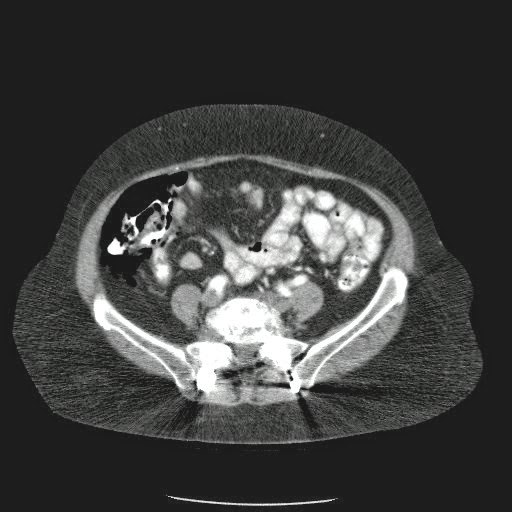

Paciente con antecedente de ALIF (Fusión lumbar intersomática anterior) 360 grados L5-S1 hace siete meses, quién presenta herida de abordaje anterior con dehiscencia de sutura, con cierre por segunda intención, quien consulta por cuadro clínico de dos días de secreción purulenta en herida quirúrgica, niega fiebre, niega otras sintomatología, refiere episodios previos similares.

Paciente en POP de ALIF L5-S1 quien presento dehiscencia de la herida abdominal con ISO superficial ya tratada, sin embargo persiste con dehiscencia y desde ayer con supuración asociado a fiebre subjetiva. Se realiza eco abdominal con colección en pared sugestiva de absceso, elevación de RFA por lo cual se considera se debe hospitalizar para manejo antibiótico, drenaje de la colección, manejo médico y vigilancia neurológica.

- ¿Hallazgos Escanografia?

2. Hay una colección de la pared abdominal en el flanco derecho, que realza en la periferia con el contraste, e intraabdominal tiene aire pero no me parece colección intraabdominal porque la grasa no está alterada.

3. Recomendado: Drs. JOSÉ M. ZUÑIGA A.1, FRANCO ORELLANA G.1, MARCELO CASTRO S.3, ROLANDO SEPÚLVEDA D.4, HORACIO RÍOS R.4, Int. VELIA SALDÍAS H.2. Neumatosis Intestinal: Caso Clínico-Radiológico. Pneumatosis intestinalis. A case report. Rev Chil Cir v.61 n.1 Santiago feb. 2009